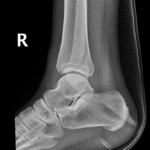

A bone is fractured when there is a break in the continuity of the bone cortex. Similar terms used to describe a fracture include broken, crack, greenstick or buckle; all are used to refer to the same thing – a broken bone. The break is often described by its location (i.e. bone) and its direction (horizontal, oblique, transverse).

- Ankle Fractures.